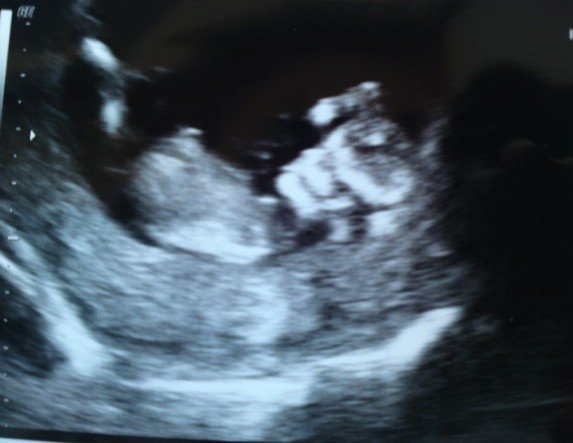

Det er jo ved at være længe siden, jeg fik et billede af en positiv test

Jeg er så glad for, at du ikke skal gå og være bekymret mere over, om det hele er som det skal være!!

Jeg er simpelthed så glad på jeres vegne - selvom det ikke bliver 6 ugers forskel denne gang